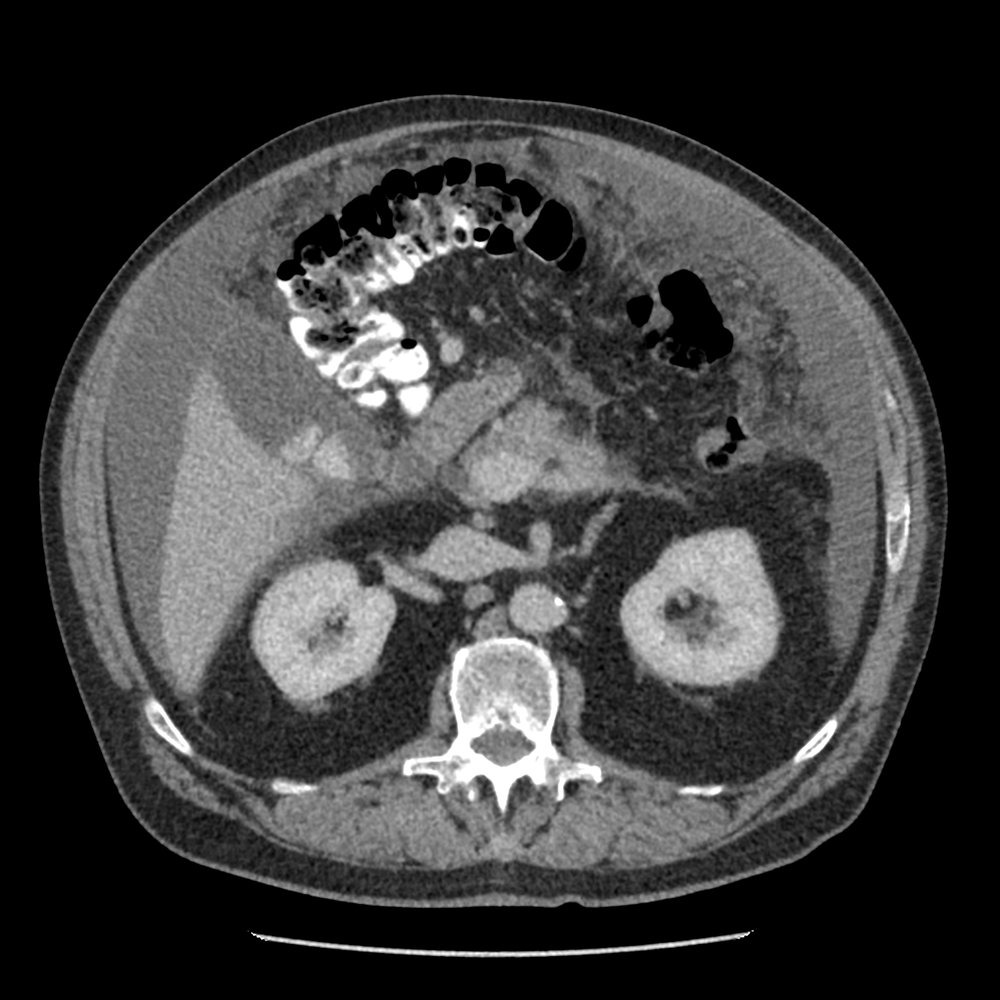

- Best staging test: CT chest/abdomen/pelvis with contrast

- CT chest/abdomen/pelvis (initial staging)